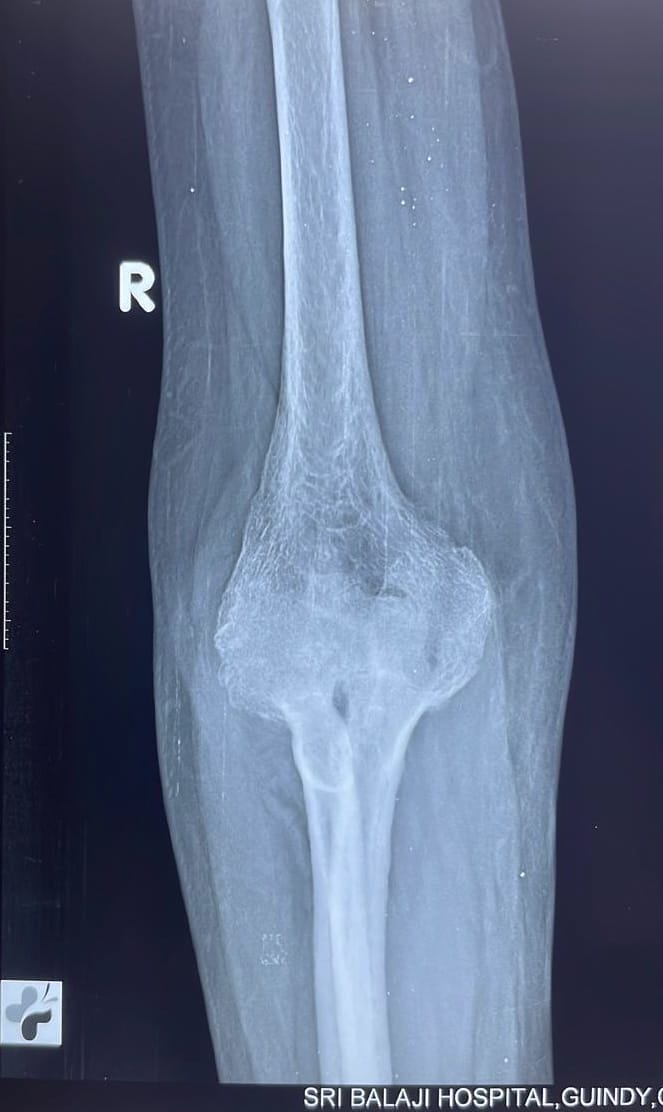

Simple X-ray of the elbow: The most basic form of imaging modality to visualise the elbow joint is the X-ray. Many (but not all) details can be obtained from viewing an X-ray. Note: An X-ray primarily reveals the bone and provides limited details. For a more comprehensive examination of the bone and the ligaments surrounding the elbow, a CT scan or an MRI scan of the elbow may be necessary.

X-ray showing severe destruction of the right elbow joint in a patient.X-ray of an elbow showing severe destruction of the right elbow joint in a patient.

X-ray showing severe destruction of the right elbow joint in a patient with rheumatoid arthritis.